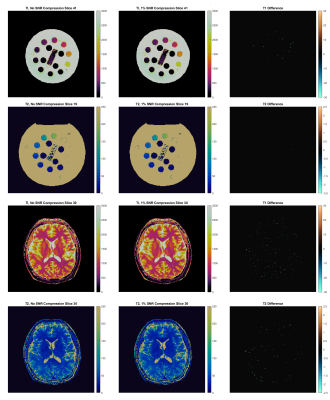

Figure 4 demonstrates the differences in T1 and T2 maps caused by SNR-constrained data compression.With compression disabled, phantom reconstructions finished in 52 seconds with mean network throughput of 138Mbps, versus 54 seconds and 70Mbps at 1% SNR compression error tolerance. Versus the maps generated with uncompressed data, compression introduced 0.00±0.09% error in T1 values and 0.00±0.04% error in T2 values.

In-vivo, online reconstructions without compression finished in 55 seconds with mean bandwidth of 212Mbps, compared to 56 seconds and throughput of 75Mbps with 1% SNR compression error tolerance. The increased bandwidth for in-vivo can be attributed to the use of additional coils. Versus the maps generated with uncompressed data, compression introduced 0.01±0.2% error in T1 values and 0.02±1.17% error in T2 values.

Comparison of reconstructions performed on uncompressed versus compressed raw datasets for both a phantom and in-vivo acquisition. In the phantom data, compression introduced 0.00±0.09% error in T1 values and 0.00±0.04% error in T2 values versus the uncompressed data, while in-vivo compression introduced 0.01±0.2% error in T1 values and 0.02±1.17% error in T2 values.